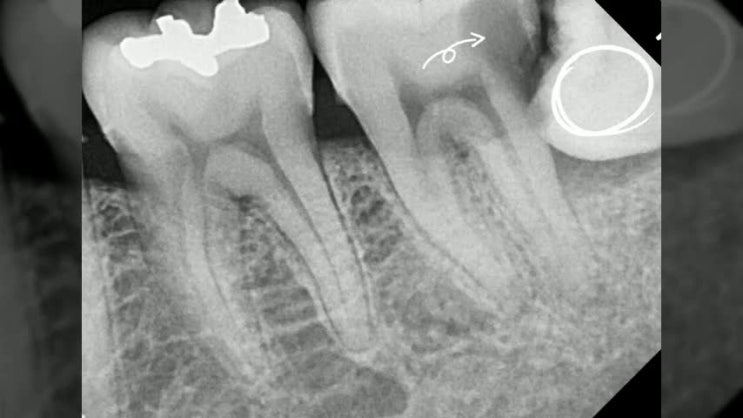

재신경치료 후기를 통한 염증제거 과정과 실패 및 성공률 ! 임플란트 하기 전 마지막 방법 feat. 비용 가격까지

재신경치료 후기를 통한 염증제거 과정과 실패 및 성공률 ! 임플란트 하기 전 마지막 방법 안녕하세요~ 행...